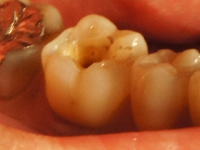

根管治療リカバリー症例

術前 ➡

術後

神経の治療後数年で再発してしまった症例。

根の先までしっかりと薬が入っておらず根の管が細くなってしまっていたのでそれをしっかりと形成し薬を入れました。

保険の治療では根の再感染は避けられないのですが、出来るだけしっかりとした治療を行うと予後が良くなる確率も高くなります。